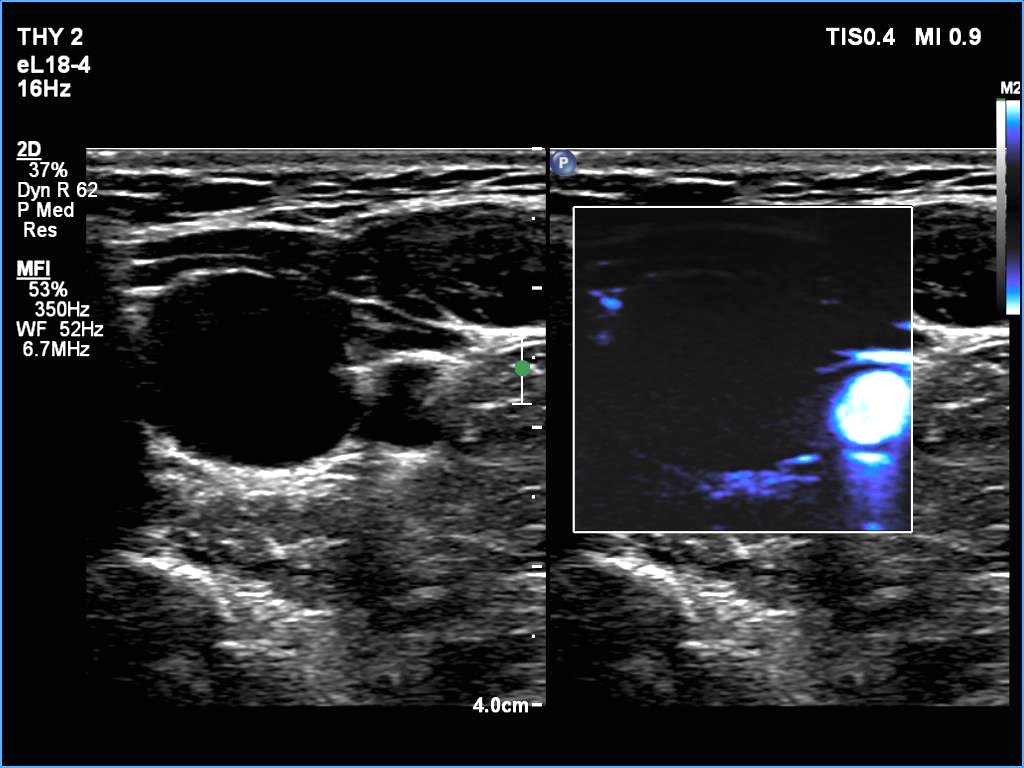

Right lobe, longitudinal scan

Lower pole of the left lobe, transverse scan, microflow imaging. There is no vacularization within the cyst.